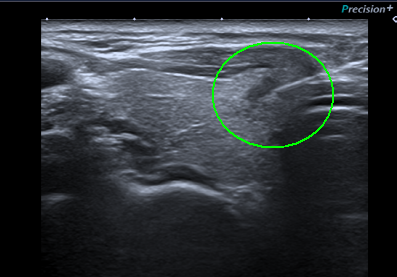

양성 결절로 진단된 증례 3

양성결절로 의심되는 소견이나 최근 커진 느낌(전경부의 불편함, 목의 이물감)이 있어 세포흡인검사를 실시하여 양성소견을 통해 확인하였습니다.